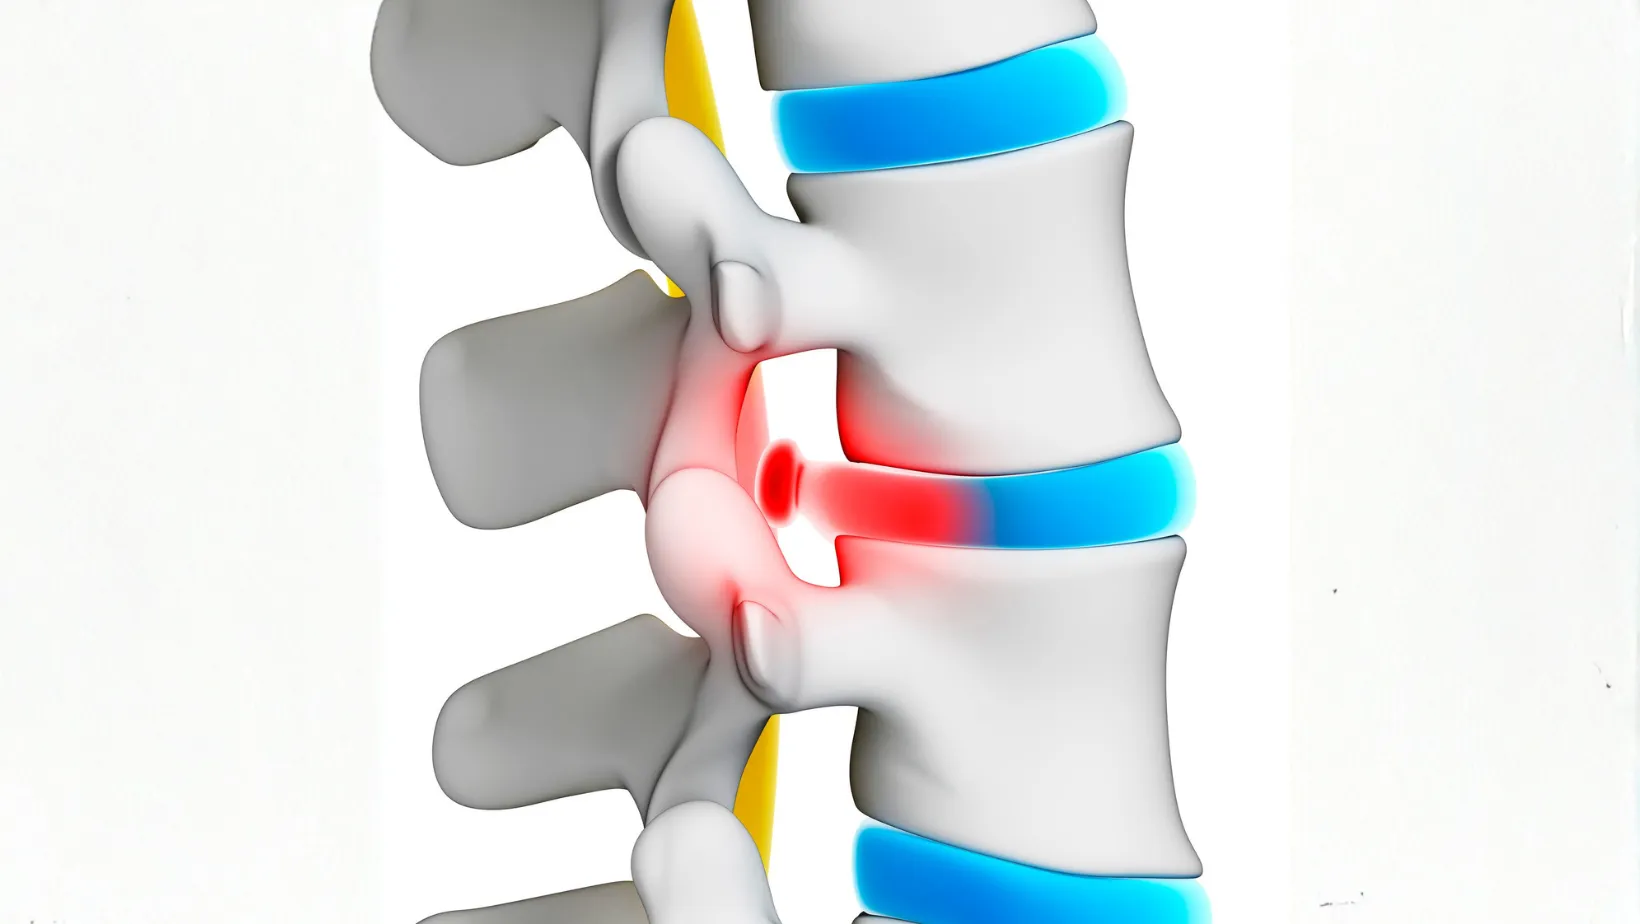

How to Heal a Bulging Disc Naturally: Treatments, Exercises & Recovery Tips

A bulging disc occurs when one of the soft cushions (called intervertebral…